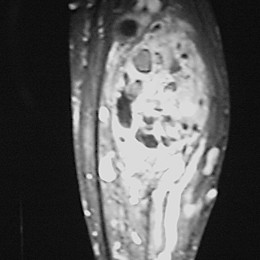

An example of an MRI is shown.

28B) Coronal MR Of Right Proximal Fibula Hemangiopericytoma